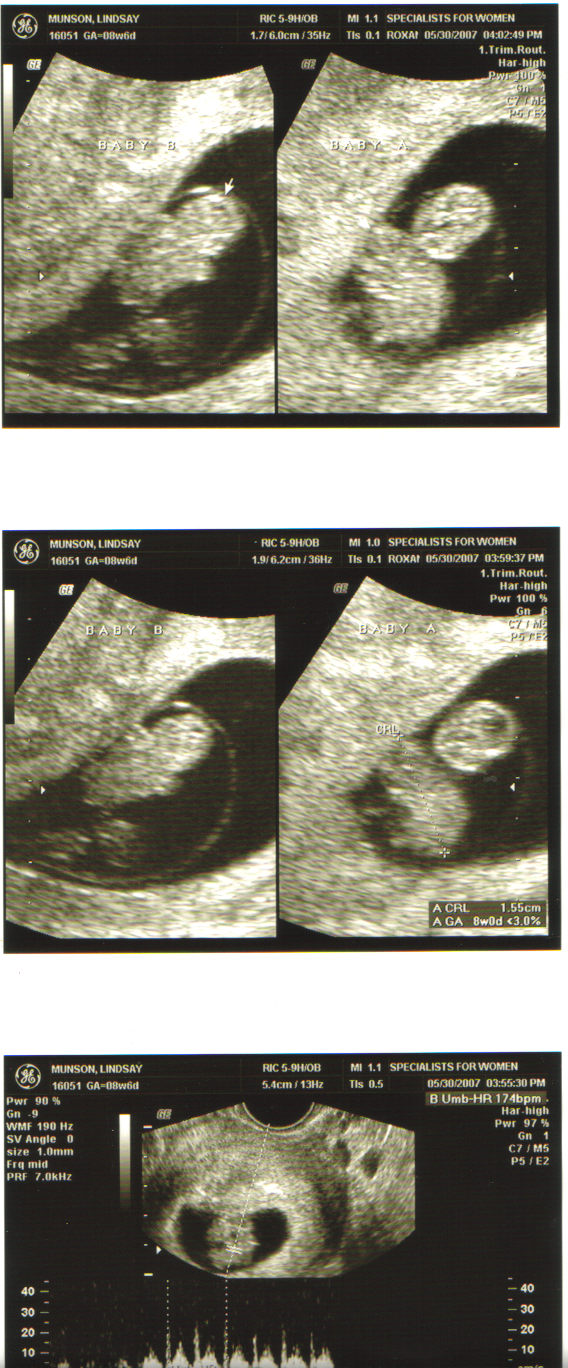

Well we just had the shock of all shocks!!! We went to the doctor today and found out we are having TWINS!!! Everyone has been giving us a hard time and joking that we were having twins and neither one of us ever entertained the thought that it would ever actually happen.

Right now they think that they are identical twins, meaning that they share the same sack, which bumps up the risk factor. But the good news is I won’t be late this time!!! I’m very excited about that! Maybe we’ll have them before the new year and get three child write-offs for taxes!!! 🙂

Right now my due date is January 3 and they babies are measuring great and their hearbeats were both strong. BJ was able to go to the appt. with me which I am so glad because I would have freaked out without him there. ah…who am I kidding….I freaked out WITH him there!